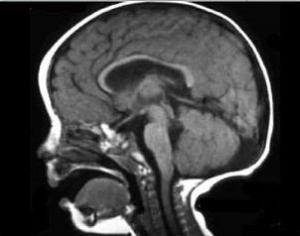

La enfermedad presenta una complejidad muy grande como para resumir sus causas. Sin embargo, básicamente puede describirse como una malformación en el mesencéfalo y en el vermis del cerebro, encargado de la movilidad de las células que comprenden el líquido cefálico.